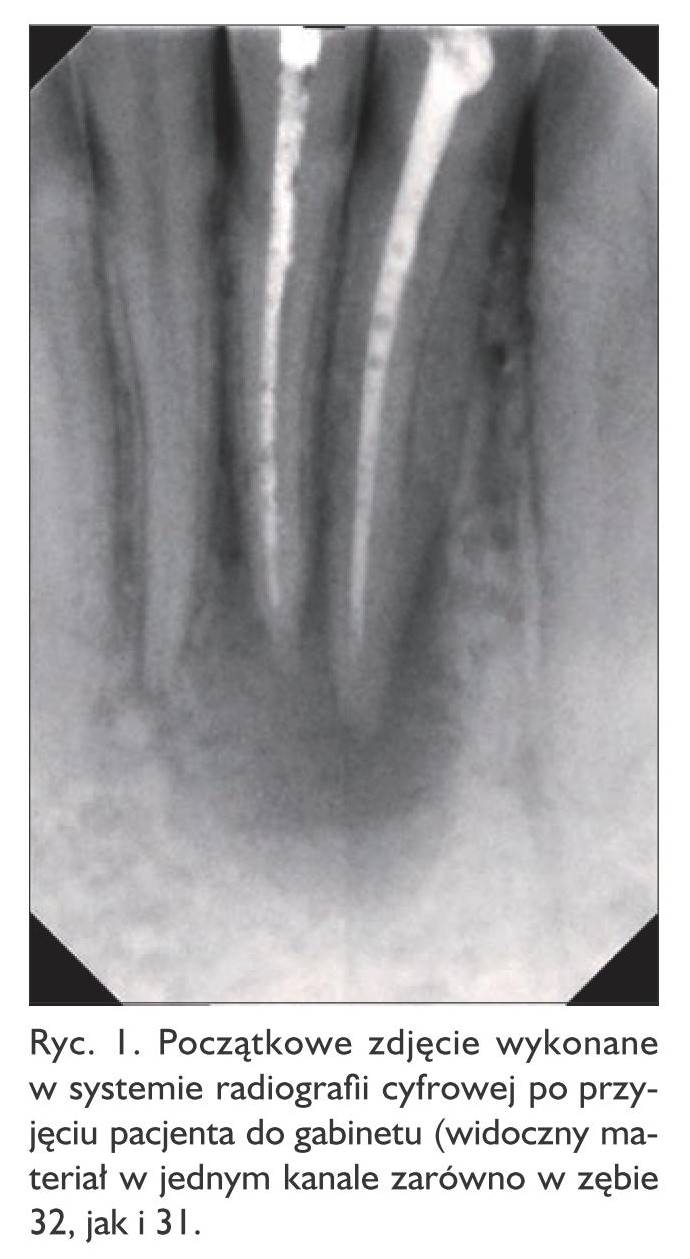

Wykonano zdjęcie rentgenowskie pantomograficzne oraz zębowe zdjęcie tej okolicy w systemie radiografii cyfrowej (ryc. 1). W kanałach zębów 32, 31 był widoczny silnie kontrastujący materiał, z rozległym przejaśnieniem wokół wierzchołków tych zębów. W znieczuleniu miejscowym, po odizolowaniu pola zabiegowego koferdamem, otwarto zęby, 5,25% roztworem podchlorynu sodu wypłukano z kanałów pastę Dexadent z jodoformem oraz zmierzono długość roboczą kanałów endometrem. Po osuszeniu kanałów odnaleziono i udrożniono kanały językowe, które do tej pory w obu zębach nie zostały opracowane. Po standardowym płukaniu z zastosowaniem 5,25% roztworu podchlorynu sodu oraz kwasu cytrynowego, z dodatkową aktywacją ultradźwiękami, do kanałów w obu zębach założono ponownie pastę Dexadent z jodoformem, a otwory trepanacyjne zamknięto cementem szkło‑jonomerowym.